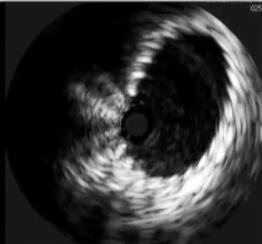

![]() if you look hard enough,如果你的眼睛睁的足够大,你就不难发现,通常下肢血栓清除后是潜在的静脉狭窄 术前的影像检查能为您提供一些线索:可能存在动脉受压的情况;或者淋巴结或其他肿块压迫了静脉。 血栓的上限通常标志着狭窄的部位。 术中血管内超声检查是最准确的。

2. 如果没有血管内超声技术,预扩张则有助于实现支架尺寸的精确测量。【Oropallo 2023】【CIRSE SOP 2014】 3. 必须确保支架输送系统能够顺利通过并完成置入操作。【Oropallo 2023】【CIRSE SOP 2014】

4. 这使得支架能够更容易地扩张。 扩张球囊产生的向外作用力比支架大 100 倍以上。 需要将狭窄的血管扣账的足够大,以便让支架能够将管壁撑得完全敞开! 这一点对于(所有)新型专用静脉型镍钛合金支架来说尤其适用,尤其是那些采用开放式细胞结构的支架,这样可以防止支架的膨胀效果不理想。【Lichtenberg 2018】